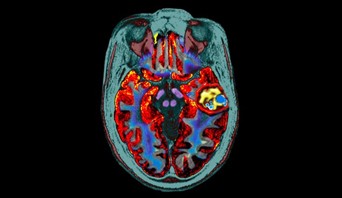

მაგნიტო-რეზონანსული გამოკვლევის სურათი აჩვენებს ტვინზე კავერნომას (ყვითლად მონიშნული).

კავერნომა

კავერნომა პათოლოგიური სისხლძარღვების ჯგუფია, რომელიც ძირითადად თავისა ტვინსა და ზურგის ტვინში ფორმირდება.